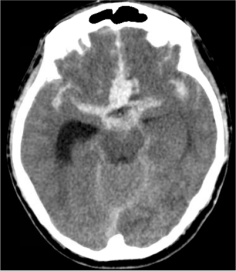

Bleeding into the subarachnoid space from rupture of a brain aneurysm. The subarachnoid space is the area between 2 layers of covering of the brain and typically contains the blood vessels of the brain as well as the cerebrospinal fluid (CSF). Aneurysmal SAH is considered a type of hemorrhagic (bleeding) stroke.

1. Hydrocephalus

Hydrocephalus is the accumulation of the cerebrospinal fluid (CSF) in the fluid-filled spaces of the brain (ventricles). In SAH, hydrocephalus occurs when the blood in the subarachnoid space blocks the normal drainage of the CSF. Hydrocephalus can lead to elevated intracranial pressures (ICPs), which results in decreased consciousness and subsequent coma if not treated immediately. A bedside procedure can be performed where a catheter is placed into the ventricle to drain the CSF. This procedure is called a ventriculostomy or external ventricular drainage (EVD).